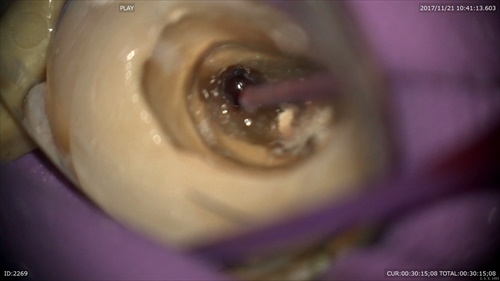

根管見えにくいですね。

マイクロで探します。重症のむし歯は皆さんこんなになっています。感染源が取れていないだけの様です。

感染源を染め出して綺麗に。

徐々に綺麗に。MB2あった。

その中(イスムス)がまた感染。マイクロエキスカで綺麗にします。

これで歯を抜かなくて済みます。